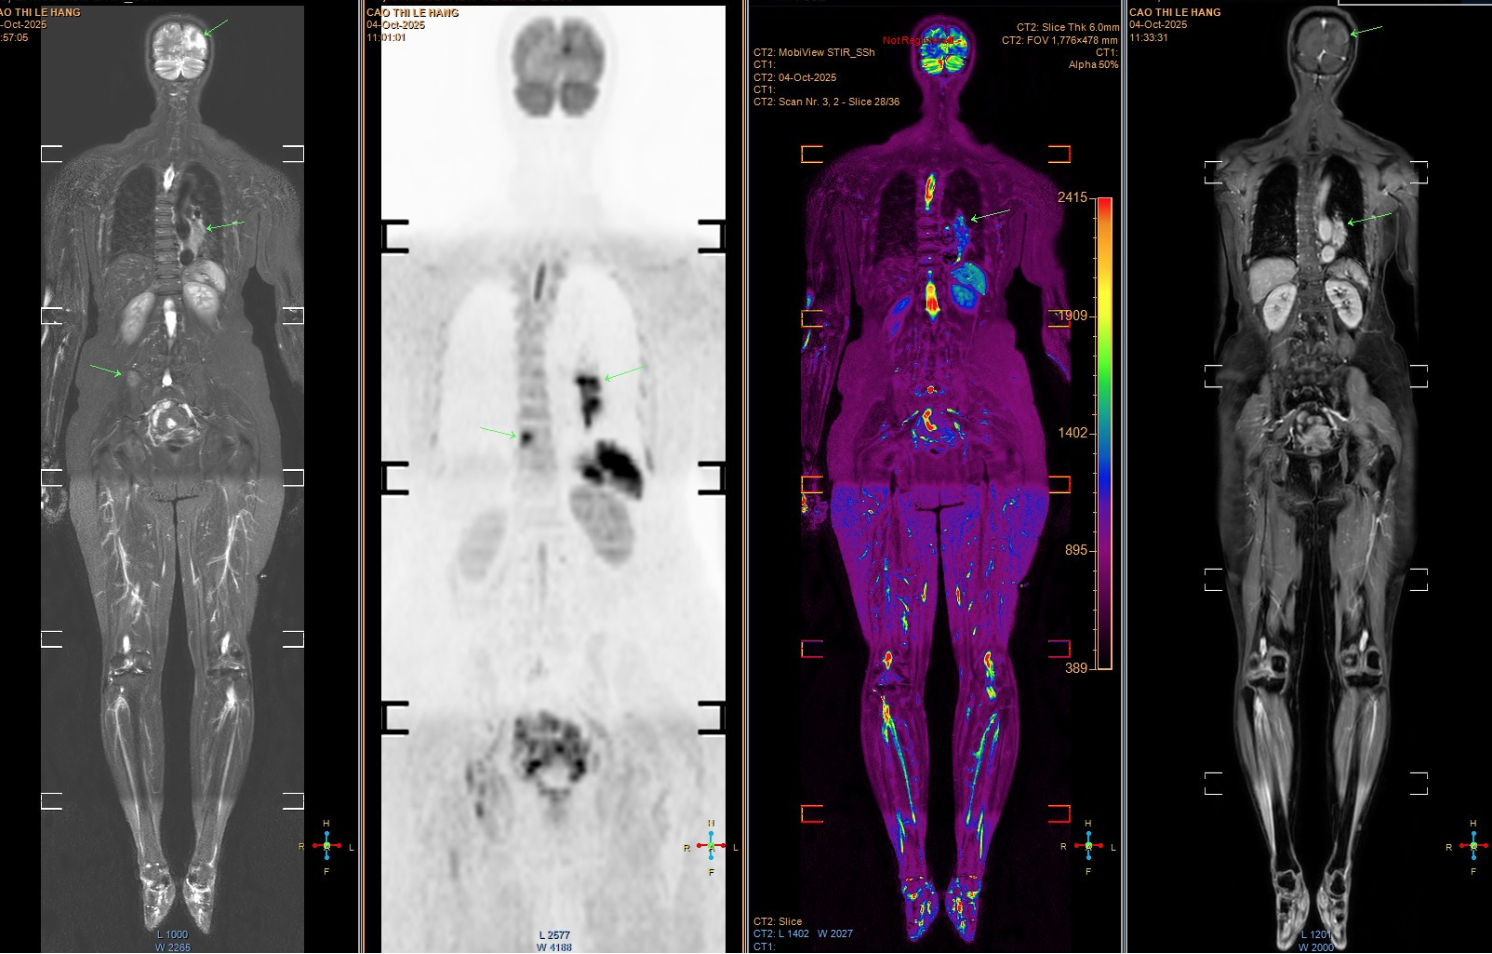

Tuy nhiên, các triệu chứng ngày càng nhiều và nặng hơn, bệnh nhân mới chịu đi khám sức khỏe. Kết quả chụp MRI cho thấy nhiều ổ tổn thương di căn dạng biểu mô tuyến. Khi chụp CT ngực, bác sĩ phát hiện một khối u lớn ở đáy phổi trái, xác định là ungthư phổi giai đoạn muộn, đã di căn sang nhiều cơ quan, trong đó có não bộ. Tiên lượng bệnh rất xấu.

Hình ảnh chụp tổn thương di căn của bệnh nhân. (Ảnh: Bác sĩ cung cấp)